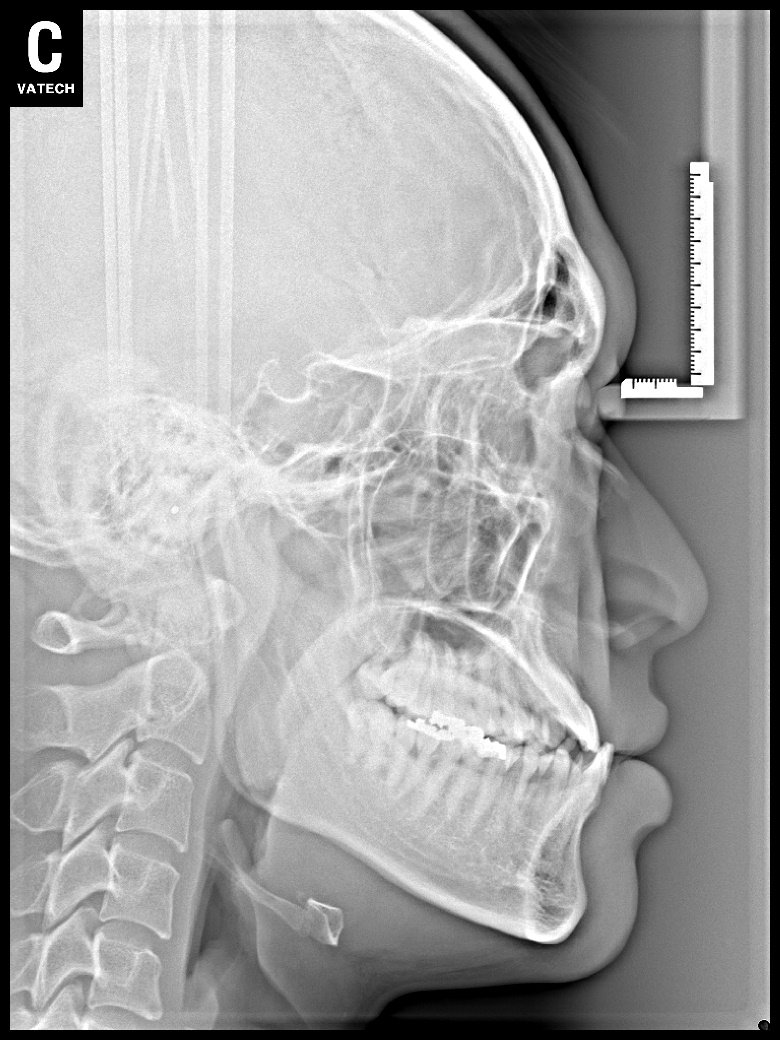

치료 전 사진입니다.